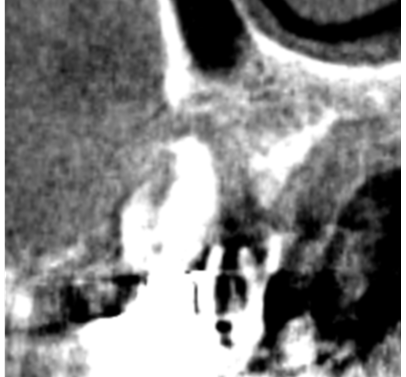

①歯槽頂よりサイナス

リフトを行いました。

術前ではインプラントを埋入する骨組織はほとんど有りませんが、

術後完全に骨内に埋入出来ました。